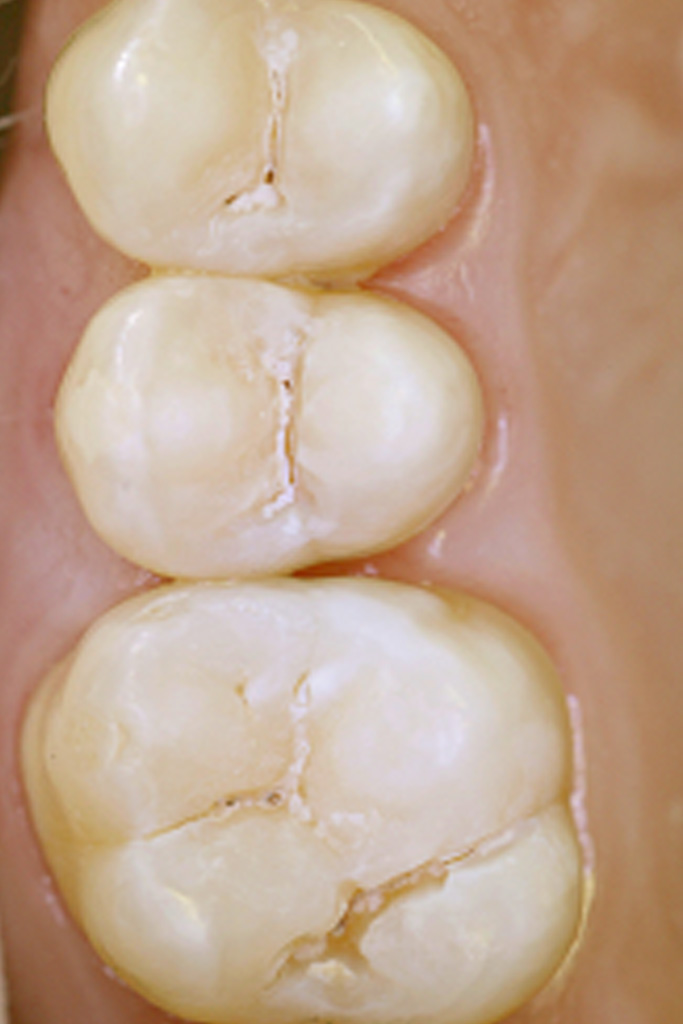

Behandlungsbeispiel:

Für den Patienten bedeutet diese Fissurensterilisation vor der Versiegelung der Fissur

mit Kunststoffen:

1. Eine echte Abtötung (=Sterilisation) der kariesverursachenden Keime in der Fissur.

2. Einen zusätzlichen Verschluß des Zahnbeins durch "Verglasung".

3. Eine zusätzliche Erhöhung der Sicherheit in Bezug auf Kariesneubildung in der Fissur